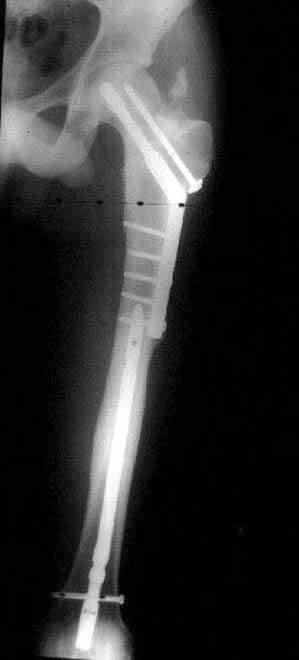

Ошибки случаются, когда игнорируются правила обследования больных с переломом бедра. Часто, когда "экономят" рентген пленки и снимают без надлежащих захватов сустава.

Одним из "золотых" правил при лечении переломов бедра в обязательном порядке до операции необходимо убедиться в отсутствии или наличии перелома шейки.

Отдельный снимок шейки или ЭОП является стандартом обследования. Все сомнительные рентген снимки проверяются тщательно дополнительными срезами КТ.

Из-за опасности вторичного смещения переломов "без смещения" во время интрамедуллярных манипуляций, особенно при ретроградном введении, необходимо каждый случай протоколировать с описанием состояния шейки после операции.

Установленный в бедро штифт, без стимуляции, не гарантирует сращение.

А не опорная болтающаяся конечность с большим рычагом усложнит состояние перелома шейки и поэтому ипсилатеральные переломы, тем более ятрогенные, очень часто осложняются двойными ложными суставами.